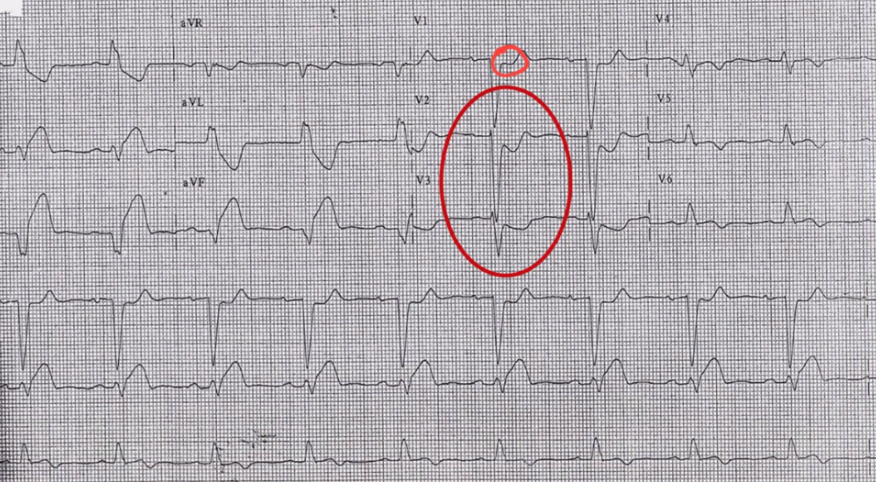

There is concordant ST depression in V3 (= Sgarbossa positive).

There is concordant ST depression in V3 (= Sgarbossa positive).

There is 1mm concordant ST elevation in I, aVL (= 5 points)

There is concordant ST depression in V3 (= Sgarbossa positive).

≥ 25% of the depth of the preceding S-wave : Revised Sgarbossa criteria

≥ 25% of the depth of the preceding S-wave : : Revised Sgarbossa criteria